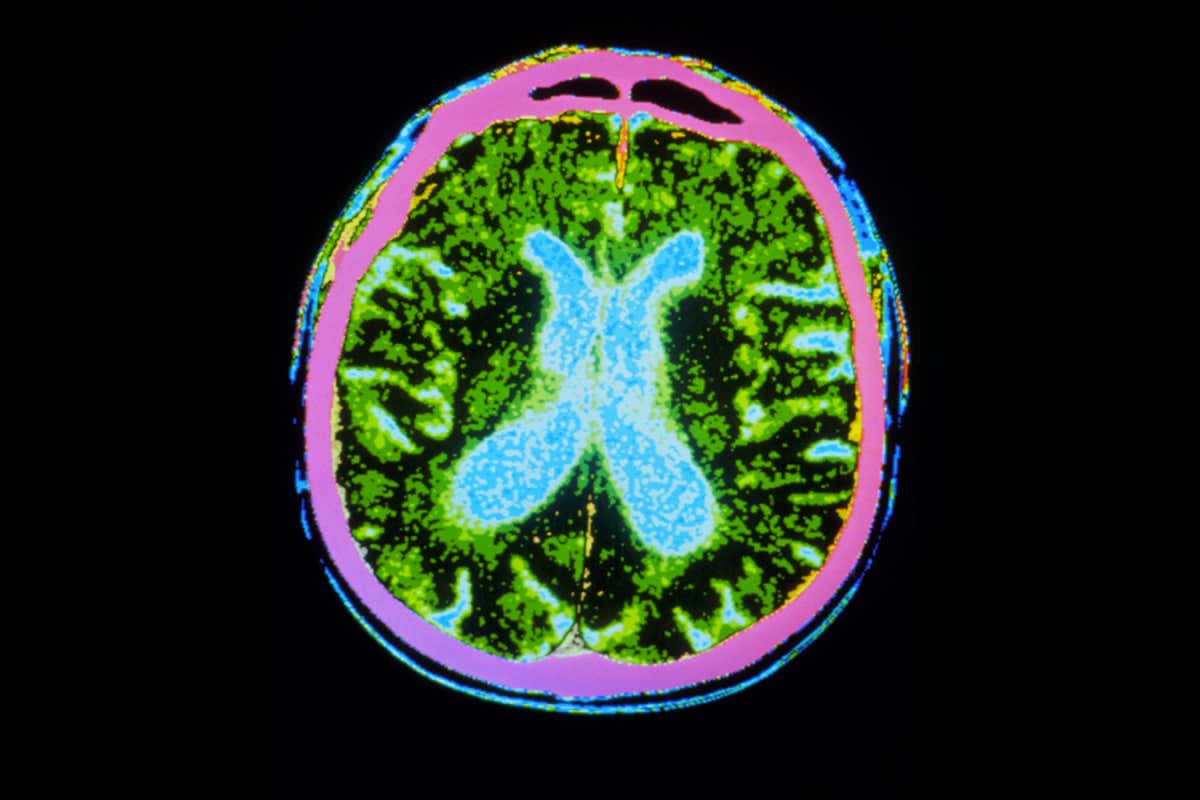

Parkinson’s disease is caused by a loss of dopamine-producing cells in the brain GJLP/Science Photo Library